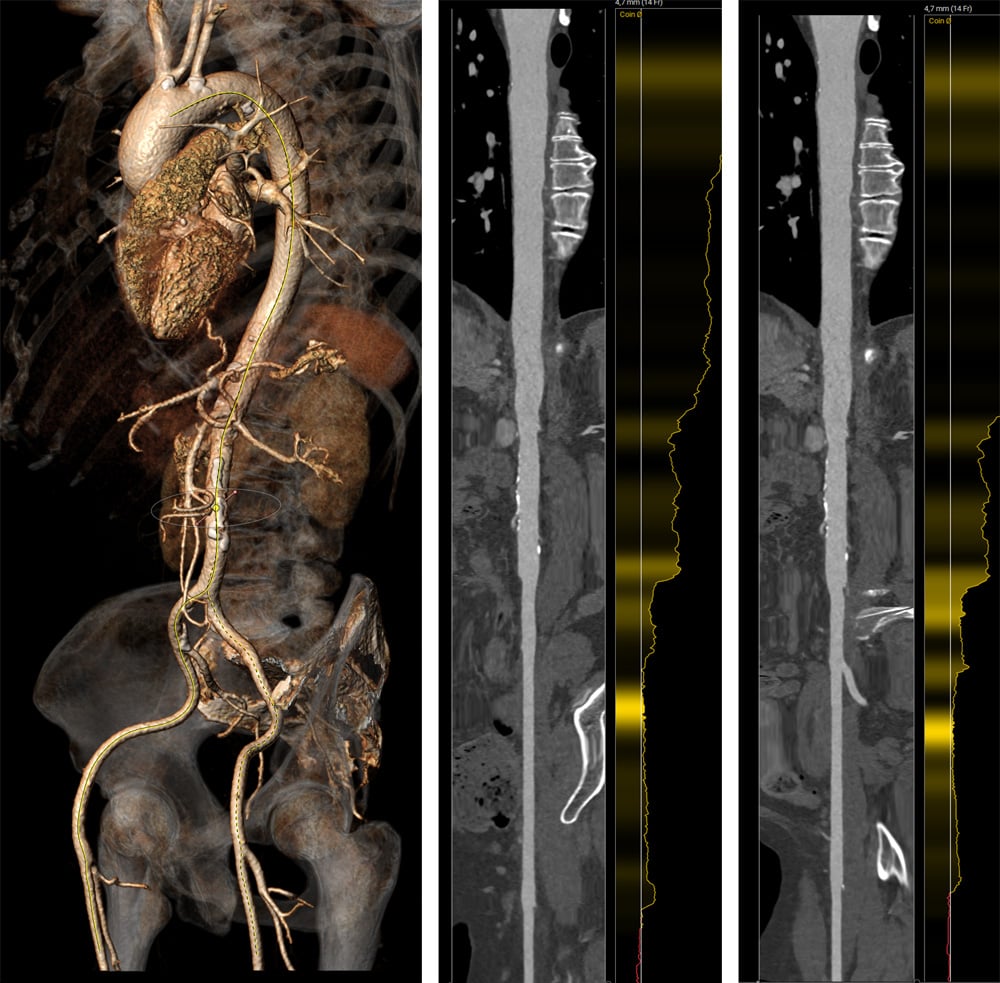

Computed tomography